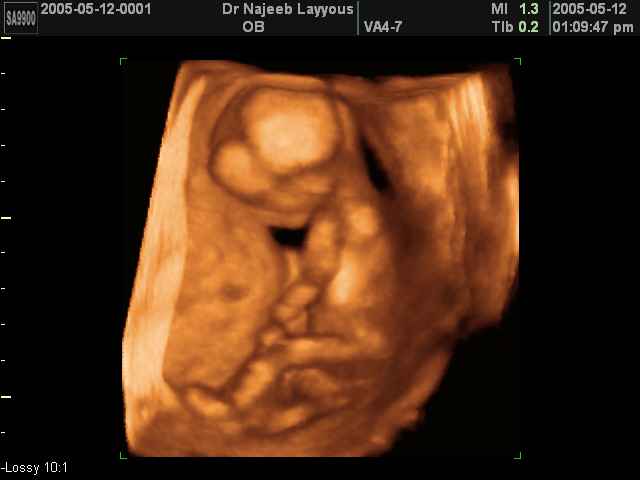

- First Trimester Ultrasound Photos

3D First Trimester Ultrasound Scan Photos ( Early Pregnancy Ultrasound Photos ) | Dr N Layyous